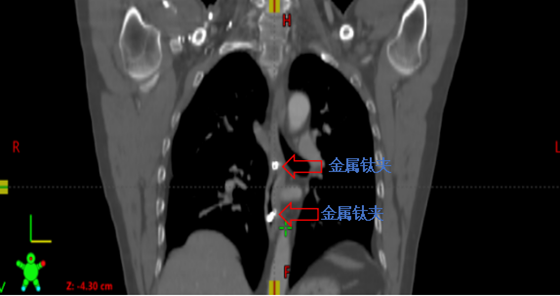

家住常德安乡县的高先生在2019年不幸罹患下咽-颈段食管癌,在湘雅常德医院肿瘤科进行了同步放化疗之后病情得到康复。近日,高先生突然胸骨后出现不适症状,进食偶感疼痛感,再次入院完...